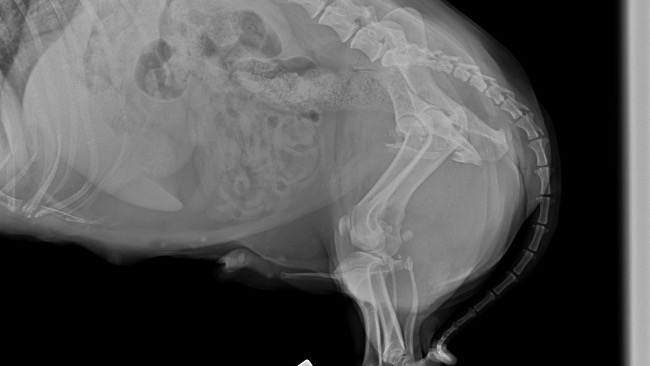

Als es scheindass sich sein Gesundheitszustand endlich stabilisiert, hatte Czaruś ein Unfall. Letzten Sonntag wurde er von einem Auto angefahren. Er wurde notfallmaßig in eine Tierklinik gebracht wo er noch am selben Tag zwiemal untersucht und diagnostiziert wurde. Er wurde außerdem am eine spezialisierte ortopedische Klinik überweisen - er hat bereits eine konsultation bei einem wunderbaren Tierarzt der Klinik Dr Hau erhalten. Leider erlitt Czaruś schwere Fakturen im Beckenbereich - Brüche des Schambeins, des sitzbeins , der linken Hüftpfanne sowie eine Bruch und Riss des linken Oberschenkelknochens.